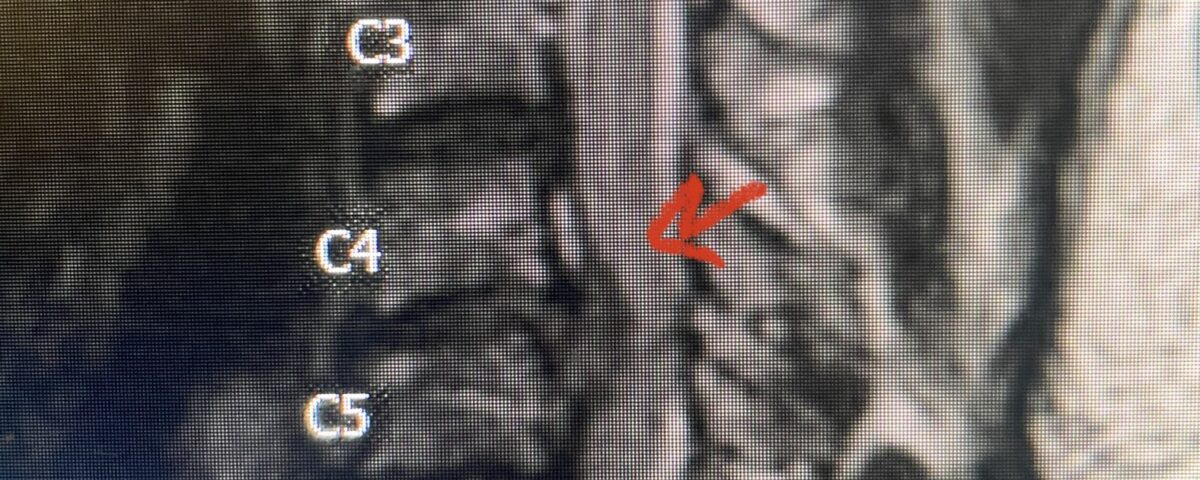

This 47-year-old male who four months prior was lifting weights developed sharp pain in his neck. After that he developed progressive numbness in his arms, neck pain and headache. He said that the right arm was worse than the left. On examination the patient had long tract weakness on the right side which included his triceps, finger extensors, hip flexors, and dorsiflexors. The patient did not have hyperreflexia. MRI (Fig. 2) demonstrated a massive, extruded disc herniation with severe cord compression. The patient because of progressive myelopathy and spinal cord compression was indicated for anterior cervical discectomy and fusion at C4-5 (Fig. 3). Patient had significant improvement of weakness and numbness post operatively.

Fig. 3 Intraoperative lateral cervical X-Ray demonstrating C4-5 ACDF